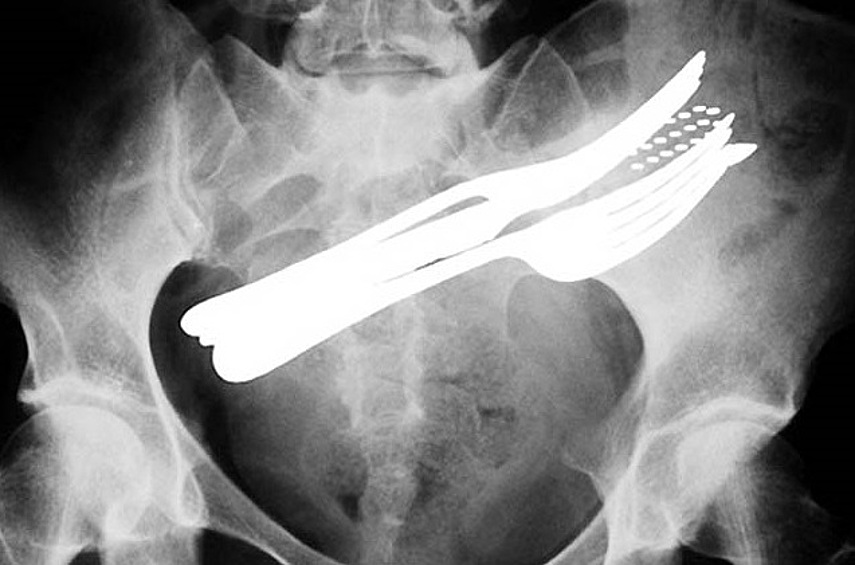

12 рентген‑фотографий, которые доказывают: идиотизм неистребим

Зачем и почему люди глотают разные странные вещи? Никто не знает точно, но медики утверждают, что таких “умников” гораздо больше, чем мы думаем.

Рентгенологи — люди с особо развитым чувством юмора. То, что они порой видят на снимках, у нормального человека вызовет настоящую истерику — а они только хмыкнут и отправят к хирургу. Что поделать, не расстраиваться же из-за каждого курьеза.